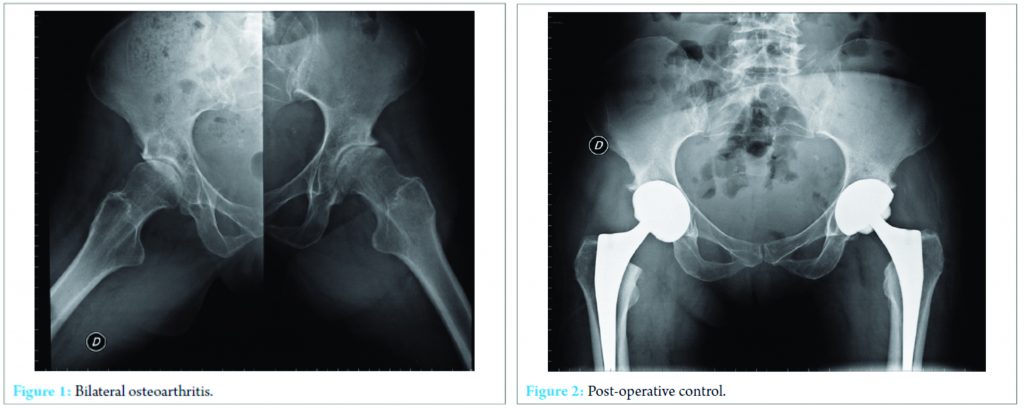

A 64-year-old Caucasian woman was referred to our hospital with a 3-year history of bilateral hip pain. 2 years prior, the patient had been diagnosed with a GH-producing pituitary adenoma and treated in 2008 by transsphenoidal surgery without radiation. Post-operative follow-up revealed a poor control of GH levels. At the time, she was treated with the administration of octreotide acetate (30 mg/month) (Sandostatin LAR, Novartis Pharma, Tokyo, Japan). On physical examination, the patient’s height and weight were 168.2 cm and 57 kg, respectively. Her blood pressure was 145/109 mmHg. Typical acromegalic features, including enlargement of the nose, lips, tongue, and extremities, were observed; however, no cushingoid features, such as central obesity, moon face, and buffalo hump, were present. Range of motion of both hips was limited in every direction. The startup test was painful, and a slight Trendelenburg gait was observed. Standard X-rays revealed a bilateral narrowing of the joint space, osteophytes, and slight sclerosis, corresponding to Kellgren and Lawrence Grade 2 hip osteoarthritis (Fig. 1). As the 6-month conservative treatment with non-steroidal anti-inflammatory acetaminophen and physiotherapy failed to improve symptoms, bilateral THA was proposed. The right hip was operated on in December 2008 and the left hip in January 2009. An uncemented, double-tapered, fully hydroxyapatite-coated stem (quadra H reg, Medacta, Castel San Pietro, Switzerland) with a modular neck and ceramic head with a 28-mm articulation was implanted through a direct anterior approach on a specialty orthopedic traction table. The acetabular component was an uncemented, porous cup with a ceramic insert (Versafit Cup CC, Medacta SA, Castel San Pietro, Switzerland).

The post-operative conventional X-ray is shown in (Fig. 2). In April 2013, the patient presented with a recurrence of right-sided hip pain. Although zones of peri-implant lucency were found on standard X-ray on both stem and acetabulum, no change in the inclination of the cup was noted. A bone scintigraphy showed an unusual fixation on the acetabular component. 2 weeks later, the patient suddenly reported extreme pain and was unable to walk. A computed tomography-scan revealed the migration of the acetabular component (Fig. 3). Samples of articular liquid were sent for bacteriological examination and culture. No evidence of infection was found. A hip arthroplasty revision was performed in May 2013 through a direct anterior approach on a traction table. Since the stem did not show any signs of per-operative instability when clinically tested, only the acetabulum was replaced with a cemented component.2 years after the revision surgery, the patient is painless and has recovered a normal range of motion.